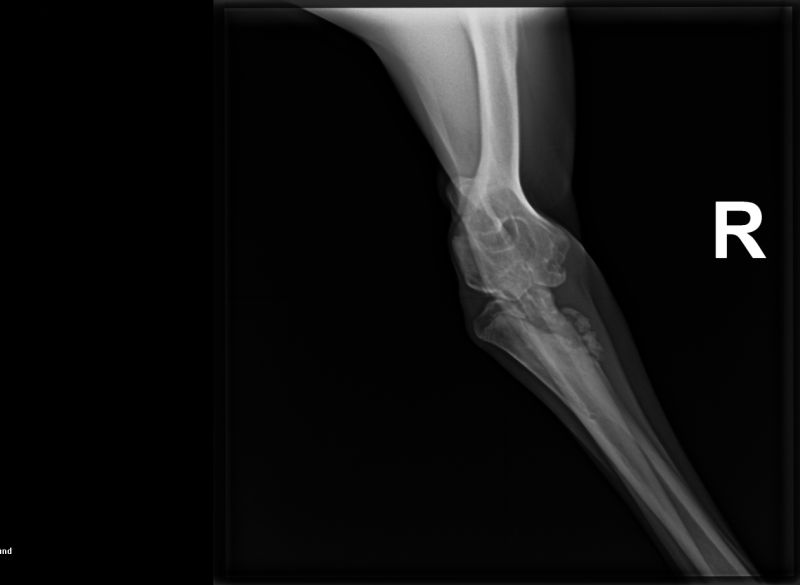

Der größte Schock allerdings für u n s, war ein Tierarztbesuch am Montag. Sonny`s rechter

Ellbogen war wesentlich dicker als sein Linker. Klar, wir röntgen, denn evtl. Interssenten sollen

wissen, was Sache ist. Die Röntgenbilder waren eine Katastrophe!!! Das Ellbogengelenk war nicht

mehr intakt, ein Knochenteil schwebt frei in neu gebildetem Kallus. Und diese Verletzung war a l t!

Bei einem 7 Monate alten Hund! Den Rest des Tages erlebte ich in einer Schockstarre. Aus Irland

Die Röntgenbilder

sind mittlerweile in mehreren Kliniken mit erfahrenen Knochenspezialisten. Wir werden hoffentlich

einen Weg finden, dieses Gelenk wieder herzustellen, bzw. Sonny überhaupt ein Leben bieten zu

können.